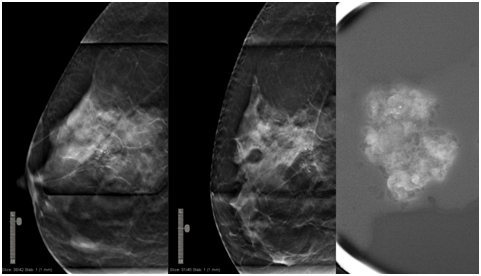

DBT-guided VAB allows use of the full detector size for imaging and provides lesion depth information without requiring triangulation. It facilitates target lesion re identification and sampling of even non-calcified masses.1,2 In our practice, the mean total procedure time was 15minutes. The mean time needed to identify and target the lesion was 2minutes (Figure 1 & 2).

Figure 2 First lateromedial (LM) acquisition in which target is located at 4 mm away from the skin (left). Second LM acquisition with rolled view, where we located virtually the target 14mm away from the skin (right). Lesion was microcalcifications with anatomopathological result of non-invasive ductal carcinoma.